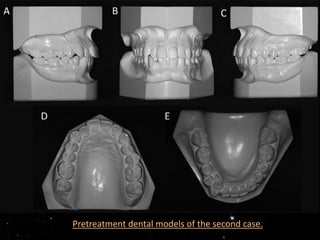

Pretreatment dental models of the second case.

Protruded maxillary and mandibular incisors (1.NA=35; 1.NB= 25;

IMPA= 93). There was a transposition between the lower right lateral

incisor and the lower right canine. The facial profile was slightly

convex. There was no tooth discrepancy. Total discrepancy of the

lower arch was calculated by adding up the arch-length discrepancy

and the cephalometric discrepancy (-8.4 mm).

Pretreatment dental modelsof the second case.

Protruded maxillary andmandibular incisors (1.NA=35; 1.NB= 25; IMPA= 93). There was a transposition between the lower right lateral incisor and the lower right canine. The facial profile was slightly convex. There was no tooth discrepancy. Total discrepancy of the lower arch was calculated by adding up the arch-length discrepancy and the cephalometric discrepancy (-8.4 mm). Two treatment alternatives were considered: 1) Extraction of four premolars with retraction of the anterior teeth and mesialization of the posterior teeth. 2) 2) Extraction of a mandibular incisor (the transposed one).